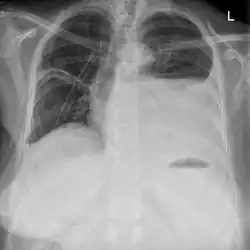

Anzeichen eines Serothorax sind eine spürbare Dämpfung bei der Perkussion des Brustkorbes, ein nur geringes oder nicht wahrnehmbares Atemgeräusch sowie eine Verschattung des erkrankten Thoraxbereiches im Röntgenbild.[7]